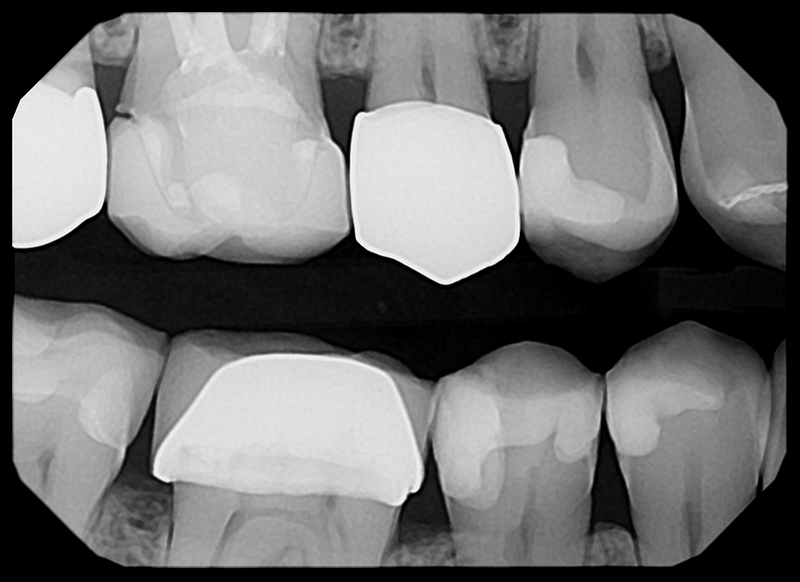

See The Clarity For Yourself

• Left Bitewing

• Mandibular Anterior

• Right Bitewing

• Maxillary Anterior

Produces a crystal clear image for confident diagnoses

The low-noise design delivers exceptional clarity even at lower doses. Keeps patients safer while improving diagnostic confidence.